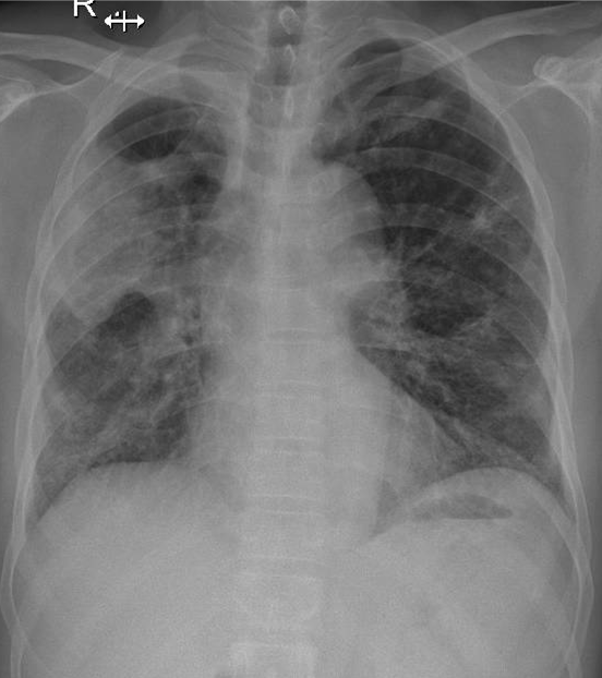

Hãy phân tích tình huống nam 62 tuổi

1-Thâm nhiễm phế nang lan tỏa hai phổi => Viêm phổi 2-U thùy trên phổi (P)